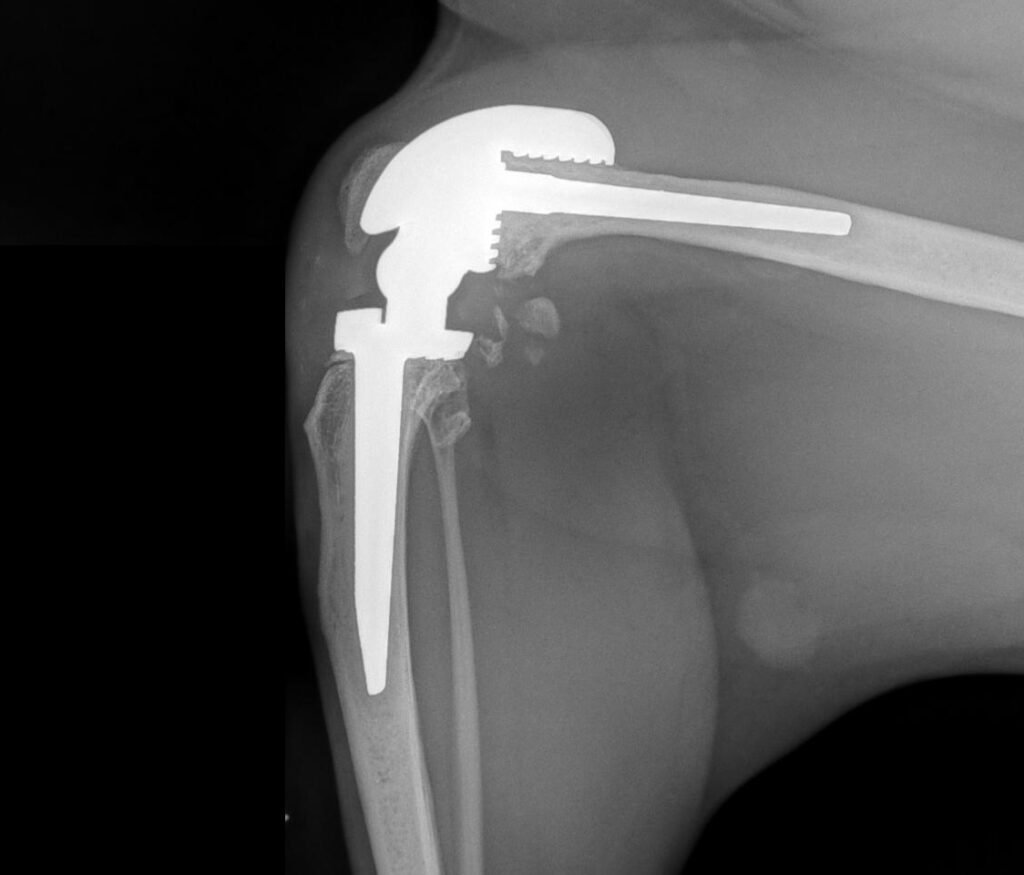

Juno’s humeral condylar fracture

Gylly’s total shoulder replacement